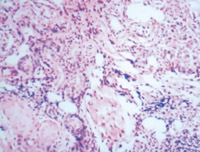

5-2-11 伤后第20天,大部门创面已由复层鳞状上皮覆盖,创面真皮层内可见增生涯跃的成纤维细胞和新生毛细血管  HE×100